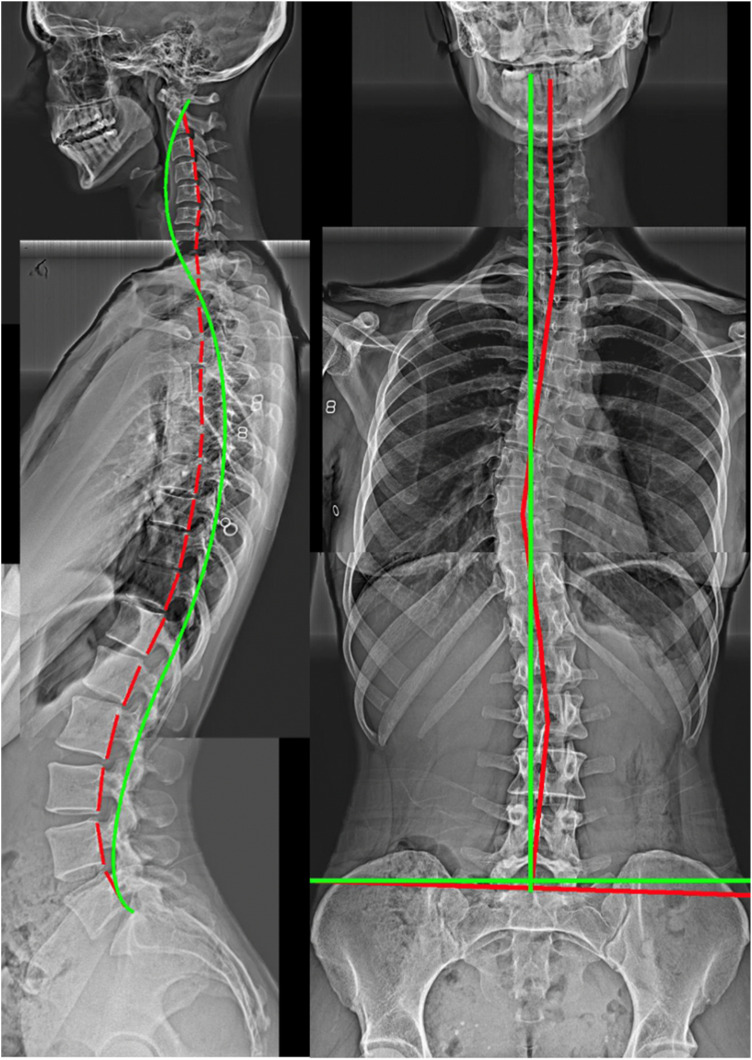

Postural alignment is a critical determinant of health status. Its degradation is associated with deformity-caused and compensation-related back pain, neurologic involvement, osteoarthritic development, as well as disability and reduced quality of life. Radiography remains the most efficient method of evaluating standard sagittal and coronal spine and pelvic metrics that are used to plan surgical and nonsurgical treatment strategies. Many current spine guidelines dissuade the use of initial screening X-rays and some chiropractic guidelines condemn repeat imaging to assess progress from treatment regimens; these are anti-scientific viewpoints that ignore alternate viewpoints and evidence. Current understanding of the relationship between different spinopelvic parameters are essential to plan biomechanically appropriate interventions that are patient-specific. There are radiographically measured parameter thresholds critically related to several spinal disorders and positive patient outcomes. Current guidelines must include a caveat for contemporary biomechanical evaluation and its consequent specific treatments and should recommend routine radiographic imaging for spine patients undergoing corrective rehabilitative interventions. The failure to radiographically diagnose spinal deformity is argued to be negligence in many cases. The prime obstacle to routine X-ray imaging lies with the presumed threat of cancer, however, this is dogma; we summarize the main evidence from recent publications why this is so.

Abstract Image